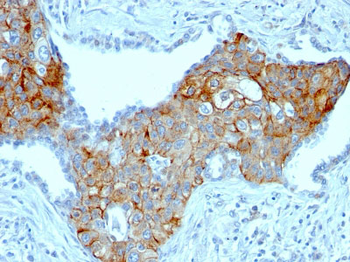

| Description | TRIM29 (Lung Squamous Cell Carcinoma Marker); Clone TRIM29/1041 (Concentrate) |

| Application notes | A431 cells. Tonsil or Squamous cell carcinoma. |